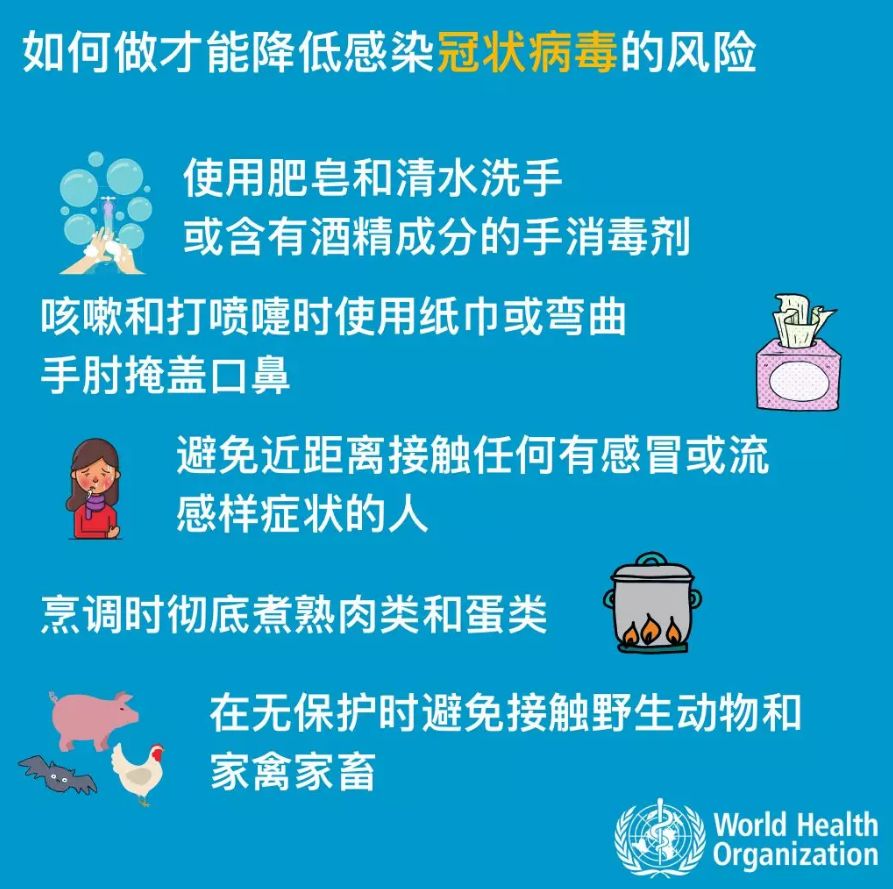

定期洗手,特别是在与病人直接接触后;有急性呼吸道感染症状(如咳嗽和打喷嚏)时用干净纸巾遮盖口鼻并擦拭干净,过后洗手;并且与病人保持适当距离。

安全饮食

餐具及食材烹饪前需洗干净;避免生吃肉类、蛋类食物,需煮熟。

(图片来源于网络)

避免接触可疑感染人群或动物

尽量避免与任何表现出呼吸道疾病症状(如咳嗽和打喷嚏)的人密切接触;避免与活的或死的农场或野生动物密切接触,尤其是疾病爆发地区。